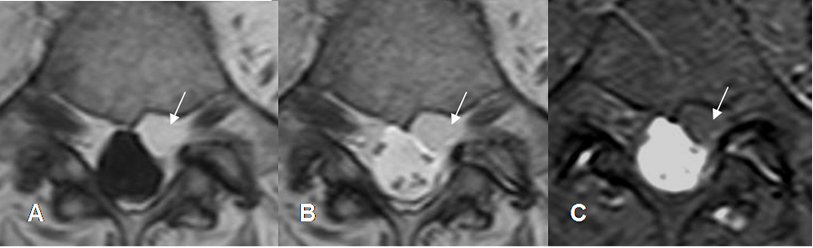

Fig 234. Lesión intradural extramedular.

A: RM axial en T1 y B: RM axial en T2. Imagen isointensa en T1 e hipointensa en T2, que ocupa la región paramediana izquierda.

Fig 235. Lesión intradural extramedular.

A: RM sagital en T2, B: RM sagital en T1 simple y C: RM sagital en T1 con contraste. Igual paciente anterior. Lesión ovalada y de bordes bien definidos, que comprime la medula espinal y realza con el contraste. En C se aprecia cola dural (Flecha gruesa), por meningioma intradural extramedular.